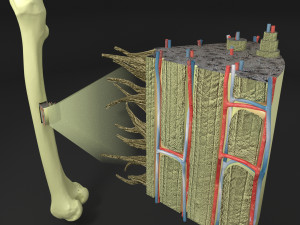

Breast anatomy histology detailed labelled precise to scale model 3D Модель

This is a 1:1 scaled model of right breast cut opened in sagittal plane to reveal its internal antomy and histology (schematic). The deeper parts and fascial layers are also depicted to give a very detailed approach to the model. The full layers starting from skin, nipple areola, till intercodtal muscles and ribs are also depicted.

breast mammary gland female chest wall anatomy human medical science reproductive genitalia muscle fascia milk nipple areola subcutaneous fatДо даного товару немає коментарів.